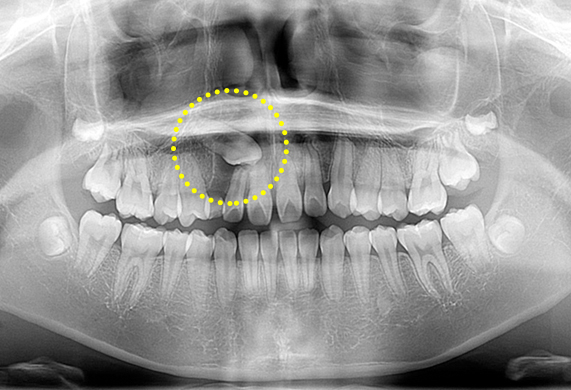

매복치

매복치는 여러 가지 원인에 의하여 치아가 나와야 할 시기가 지나도록 잇몸 안에서 못 나오고 있는 것을 말합니다. 좌우 치아가 나는 시기가 6개월 이상 차이가 나면 한 번쯤 치과에서 방사선 사진 촬영 검사를 받아볼 필요가 있습니다.

매복치 교정 CASE

-